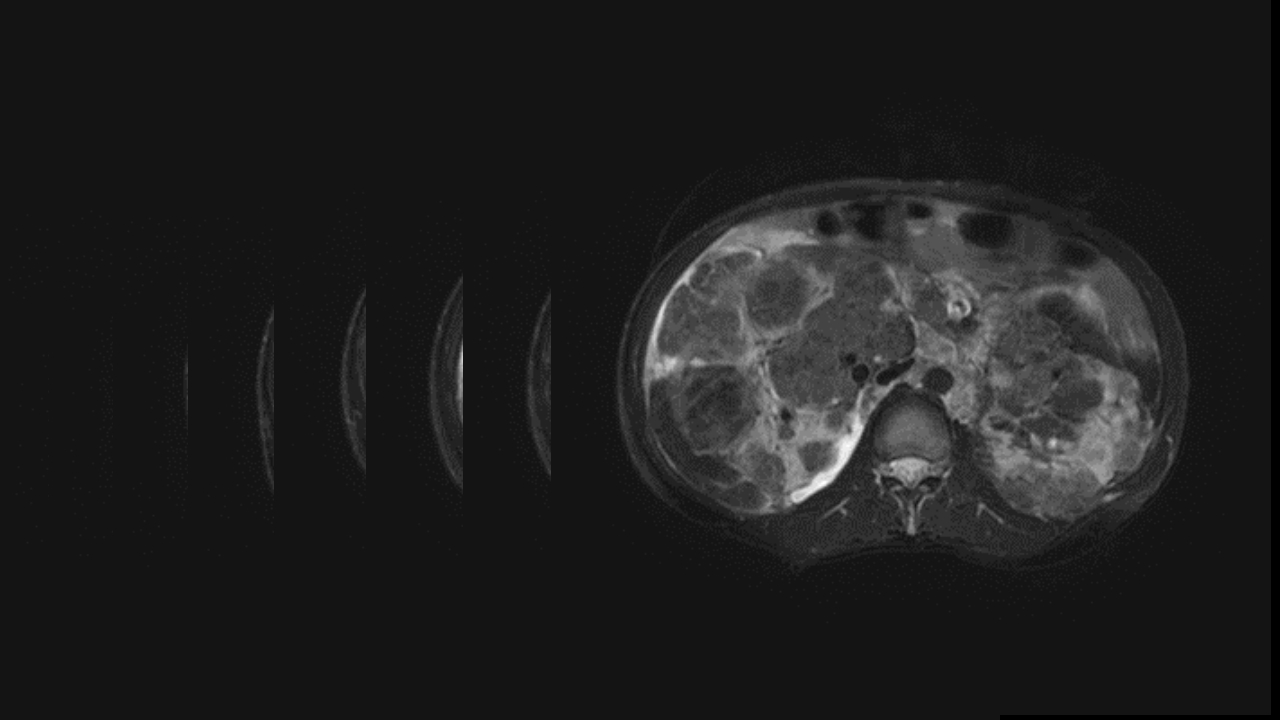

肺淋巴管肌瘤病合并双侧巨大肾血管平滑肌脂肪瘤(X线、CT、MR)